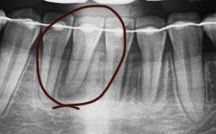

교정 끝난 직후에 파노라마 사진을 찍었는데 그 당시에는 뿌리에 염증있는 것 처럼 보였는데 5년정도 지난 지금 파노라마에는 또 안보입니다. 혹시 생겼던 염증이 사라진건가요? 가끔씩 해당 치아가 시리긴 했는데 치과에서는 잇몸이 얇아서 그렇다고 하시곤 염증은 없다 하셨거든요 원인이 뭔가요? 그리고 뿌리염증처럼 보이는게 왜 사라진걸까요? 교정 직후라서 잇몸이 안좋아서 그런가요?

• 2번 째 사진

염증이 아니고 치아가 교정을 하게되면 힘을 받아서 주변잇몸뼈가 녹아서 사진처럼 보일수 있습니다. 교정이 끝나서 안정이 된거 같습니다.

교정을 하게 되면 교정력이 치아에 가해지면서 치아 주변 조직으로 미세하게 염증이 생기면서 치아가 이동하게 됩니다. 이런 염증은 치아가 이동하고 나면 없어지는 경우가 많습니다.

치아가 교정력에 의해서 이동하면서 뼈가 소실되고 생성되는 과정에서 그렇게 나타나기도 합니다.